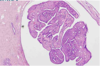

Q

What is this?

A

Intraductal papilloma - histology. Large ducts which is being dilated. Capillaries within them.